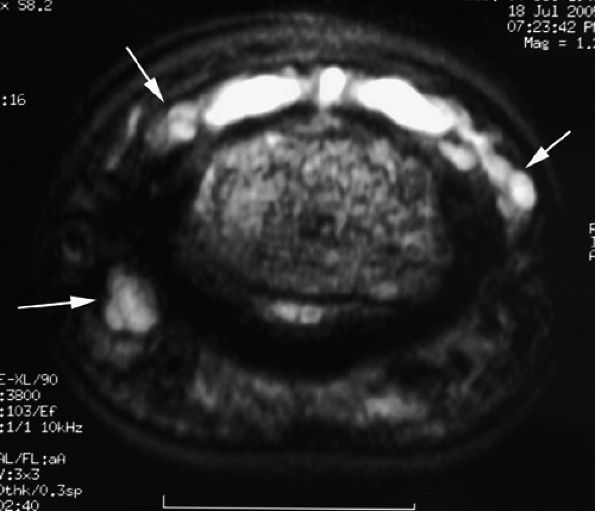

FIGURE 11.22 ● Associated injuries of the volar plate and a collateral ligament of the PIP joint. (A) Sagittal T1-weighted and (B) axial post-contrast fat-suppressed T1-weighted images show proximal injury of the checkreins of the volar plate with associated synovitis (white arrows). Continuity of the central slip of the extensor tendon is seen (arrowheads), and there is a tear of the radial collateral ligament (asterisk).